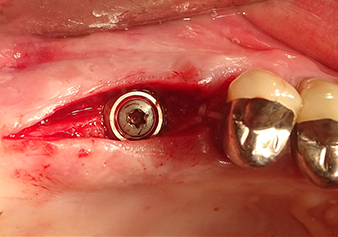

Затем, с помощью инструмента I2A (диаметр 2,0 мм), дно пазухи перфорировалось периодически и в минимально возможном диапазоне. Этот специфический пьезохирургический метод гарантирует, что мембрана Шнейдера не будет повреждена. При использовании Z25P, мембрана уже была слегка приподнята охлаждающей жидкостью, подаваемой через наконечник инструмента (рис. 3). Во избежание высокого давления в ложе имплантата, количество охлаждающей жидкости составляло не более 50%.

Подготовка ложа имплантата и наращивание

После промежуточного контроля (рис. 4) был проведен еще один этап подготовки (рис. 5). За тем, с помощью гидравлического инструмента Z35P мембрана была поднята в нужное положение (рис. 6 и 7). Далее, следовала дальнейшая пьезохирургическая подготовка ложа для имплантата, завершенная с помощью ротационного бора и лопаточной фрезы до диаметра имплантата 4,8 мм. Перед установкой имплантата под мембрану Шнейдера был введен аугментационный материал (размер частиц около 0,8-1,6 мм) (рис. 8).